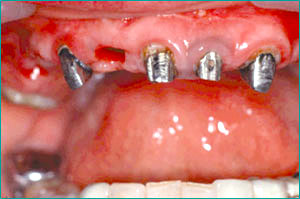

CASE1: 前歯がほとんど抜けた症例

主訴:ブリッジが駄目になり、残りの歯が4本しかない。これを利用してインプラントを入れてほしい。(職業 主婦/女性)

4本の歯を利用して上顎に6本のインプラントを入れる。 審美性の回復を目指す。

インプラントとセラミックの歯を入れる。